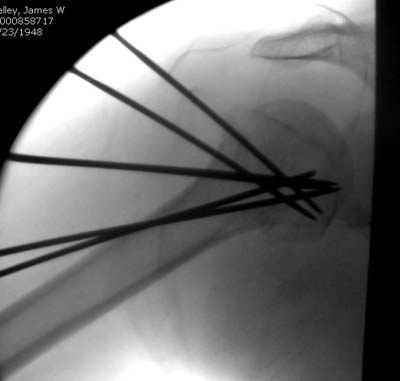

Женя, а как ты водишь спицы, в смысле, как делаешь входное отверстие, и как в него проводишь V-спицу? А то о дна из спиц, та, у которой не дошла до головки одна палочка буквы V, как-то выглядит на рентгенограмме, как будто или через очень большое отверстие введена, или каждая половинка через отдельные отверстия.

Мне кажется, проблема в том, что не все концы спиц зашли в головку, и зашедшие - недостаточно далеко прошли.

Спицы провожу по передней и задней поверхностям плечевой кости через 4,5 мм отверстия на разных уровнях.

Идеей презентации случая была демонстрация важности постоп Рг - хотя казалось бы все было сделано под флюороскопическим контролем и интраоперационно подозрений на нестабильность не возникло, а такая вот

неожиданность...

Уточни - обе части буквы V вводишь в одно отверстие? А то по снимкам выглядит, что в разные.

V-спица проводится через 4,5 мм отверстие. Видимо, из-за разной длины вторая половина спицы *пролетела* мимо отверстия, что и привело к вторичному смещению костных фрагментов.